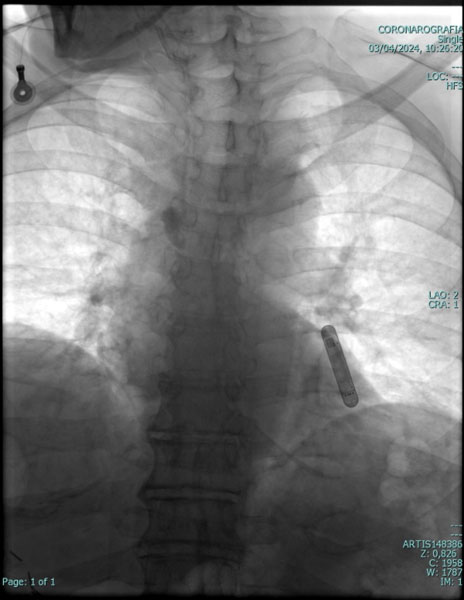

LOOP-RECORDER

Il cosiddetto “loop recorder” è un piccolo dispositivo, grande meno di un accendino da tasca (misure esatte: 62 x 19 x 8 mm), in grado di registrare il ritmo del paziente fino a un massimo di tre anni. Tale dispositivo viene inserito sotto la cute, con una piccola incisione di circa 2 cm, in anestesia locale, ed alloggiato solitamente sotto la clavicola (in modo da essere praticamente invisibile). L'apparecchietto è in grado di registrare e memorizzare sia anomalie del ritmo cardiaco in modo automatico, sia, in presenza di sintomi, l'elettrocardiogramma su comando del paziente (con un apposito telecomando esterno).

Questo dispositivo trova la sua principale applicazione, nella pratica clinica, nei pazienti con svenimenti di origine inspiegabile o con palpitazioni di breve durata, difficili da documentare con l'elettrocardiogramma tradizionale; può anche essere utilizzato nel monitoraggio a lungo temine dei pazienti con aritmie a basso/medio rischio.